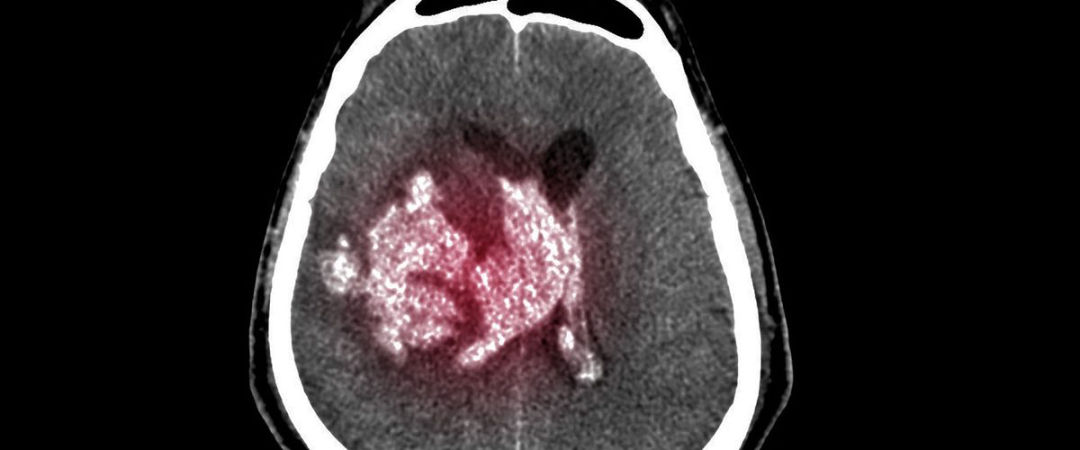

Es una acumulación de sangre entre la cubierta del cerebro (duramadre) y la superficie del cerebro.

Un hematoma subdural es a menudo el resultado de un traumatismo craneal grave. Este tipo de hematoma subdural se encuentra entre el más letal de todos los traumatismos craneales. El sangrado llena la zona cerebral rápidamente, comprimiendo el tejido cerebral. Esto a menudo ocasiona traumatismo craneal y puede llevar a la muerte.

Con cualquier hematoma subdural, las pequeñas venas que están entre la superficie del cerebro y su cubierta externa (la duramadre) se estiran y se rompen, permitiendo que la sangre se acumule. En adultos mayores, las venas a menudo ya se han estirado debido al encogimiento cerebral (atrofia) y se lesionan más fácilmente.